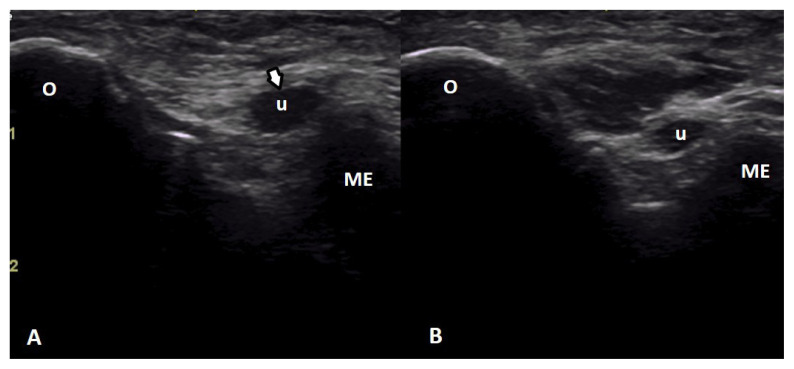

Results: While the shoulder joint accounted for the majority of joint pain detected in 23 patients, bursitis was the most common sonographic pathology. As a result of clinical and sonographic evaluations, it was determined that 29 patients had overuse syndrome. The likelihood of developing overuse syndromes increased with longer daily wheelchair use (OR = 1.666; p = 0.048) and high lesion level (OR = 12.01; p = 0.052). It decreased with the SF-36 pain score (OR = 0.943; p = 0.027).

Conclusion: The shoulder joint was the most commonly affected area in terms of pain, sonographic findings, and overuse syndrome. Prolonged daily wheelchair use, thoracic-level lesions, and lower SF-36 pain subscale scores might be determinants of the development of upper extremity overuse syndromes in paraplegic wheelchair users.